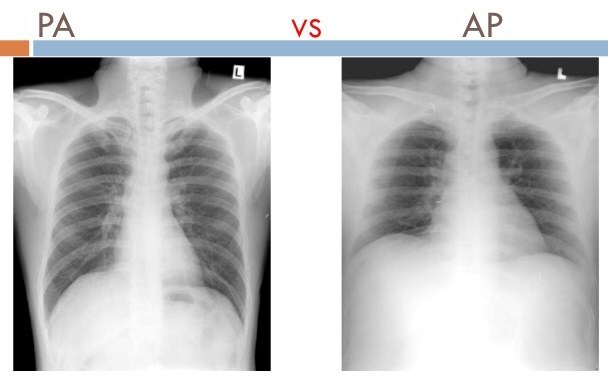

How are chest X-rays on ambulatory patients routinely done?

A

• Patient’s chest up and against the firm holder.

• The X-ray passes from the back and exits in front to the chest.

• This is called a PA projection (posterior to anterior).

• AP Projection (anterior to posterior)

For interpretative purposes, what is the main difference between an AP and PA projection?

• The heart will be magnified on an AP projection.

• This is the because the projection of the heart is farther from the film and the X-ray beam diverges as it goes farther from the X-ray tube.